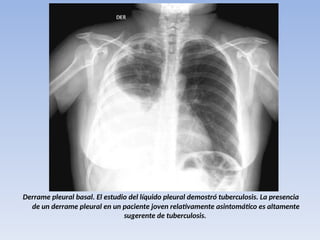

AFECTACIÓN PLEURAL

10% de los casos, mas frecuentes entre los 15 a

30 años primaria.

El Derrame Pleural tiende acumularse

lentamente y sin dolor, la mayoría son

unilaterales.

El resultado final es la presencia de una

restitución total del espacio pleural o

simplemente del ángulo costofrenico

Derrame pleural basal. El estudio del líquido pleural demostró tuberculosis. La presencia

de un derrame pleural en un paciente joven relativamente asintomático es altamente

sugerente de tuberculosis.